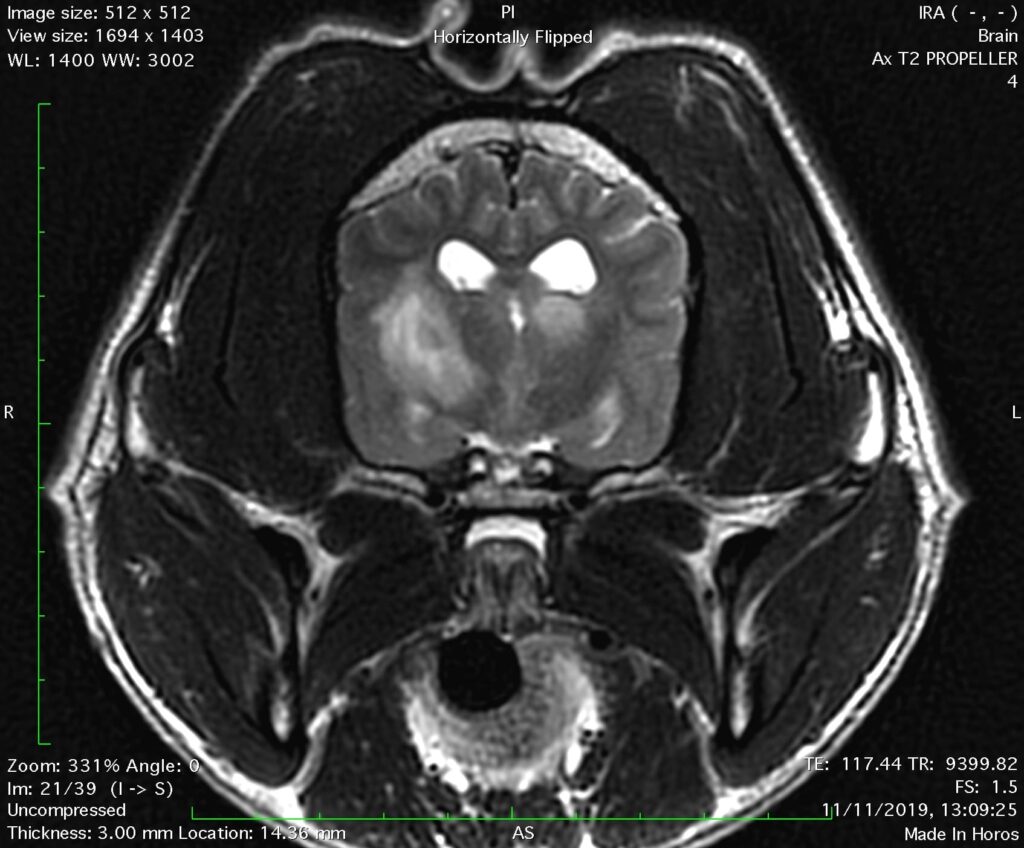

Εγκάρσια τομή του εγκεφάλου με ακολουθία Τ2. Απεικονίζονται πολυεστιακές ενδοπαρεγχυματικές αλλοιώσεις αυξημένης έντασης του σήματος με ασαφή όρια, σε σκύλο με μηνιγγοεγκεφαλίτιδα αγνώστου αιτιολογίας (MUO).

Στην MRI, οι φλεγμονώδεις αλλοιώσεις απεικονίζονται υπέρπυκνες (ανοιχτόχρωμες) στις ακολουθίες Τ2 και FLAIR και υπόπυκνες (σκουρόχρωμες) ή με την ίδια ένταση σήματος στην ακολουθία Τ1 χωρίς σκιαγραφικό μέσο, σε σύγκριση με το φυσιολογικό εγκεφαλικό παρέγχυμα. Μετά τη χορήγηση σκιαγραφικού μέσου (γαδολίνιο, gadolinium), απεικονίζεται ποικίλου βαθμού πρόσληψή του σε περιοχές με αλλοιώσεις στην ακολουθία Τ1. Ο εμπλουτισμός των αλλοιώσεων με σκιαγραφικό μέσο οφείλεται στη ρήξη του αιματοεγκεφαλικού φραγμού, με συνέπεια τη διάχυση του σκιαγραφικού μέσου στην περιοχή των αλλοιώσεων.

Τα πιο χαρακτηριστικά ευρήματα της κοκκιωματώδους μηνιγγοεγκεφαλίτιδας, στη MRI, είναι οι υπέρπυκνες (ανοιχτόχρωμες) περιοχές με πολυεστιακή ή διάχυτη κατανομή και ανώμαλη περιφέρεια στην ακολουθία Τ2 και FLAIR. Στην ακολουθία Τ1 με σκιαγραφικό μέσο απεικονίζεται ποικίλου βαθμού πρόσληψη του σκιαγραφικού μέσου. Παρότι οι ιστοπαθολογικές αλλοιώσεις της κοκκιωματώδους μηνιγγοεγκεφαλίτιδας εντοπίζονται στη λευκή ουσία, τα απεικονιστικά ευρήματα στην MRI κατανέμονται τόσο στη λευκή όσο και στη φαιά ουσία.

Τα συχνότερα απεικονιστικά ευρήματα της νεκρωτικής μηνιγγοεγκεφαλίτιδας στην MRI είναι: ασύμμετρες πολυεστιακές αλλοιώσεις στα εγκεφαλικά ημισφαίρια, οι οποίες προσβάλλουν την φαιά και την λευκή ουσία, με ποικίλου βαθμού πρόσληψη σκιαγραφικού στην ακολουθία Τ1. Μπορεί να παρατηρηθεί απώλεια του διαχωρισμού μεταξύ φαιάς και λευκής ουσίας. Οι αλλοιώσεις παρουσιάζονται με σήμα υψηλής έντασης στην ακολουθία Τ2.